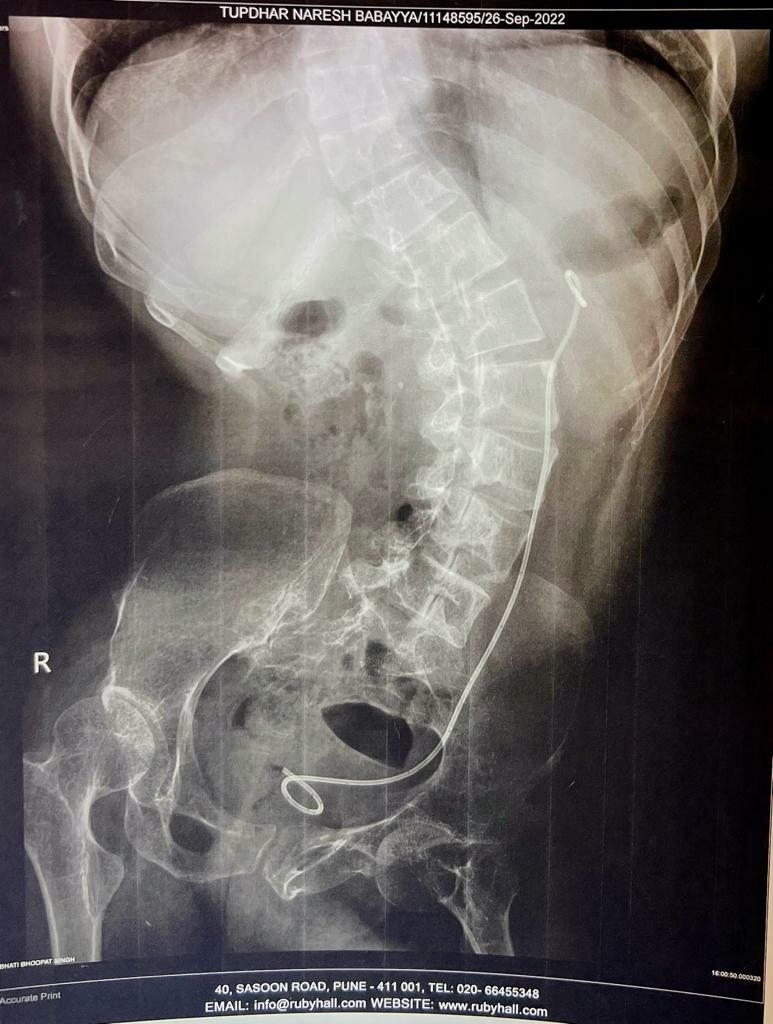

Acute renal failure with Obstruted Uropathy - Dr. Bhoopat Bhati

M60 was Admitted to ICU Care with blood in urine with Acute renal failure with Obstruted Uropathy. Investigation showed 2D Echo 18% EF   DTPA sca...